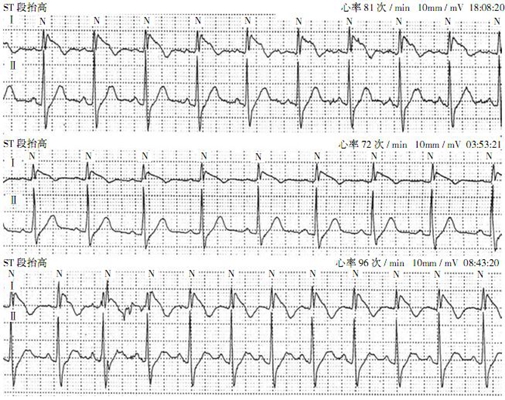

預激綜合症圖片

預激綜合症相關文章

預激綜合症相關問答

A:預激綜合徵典型的心電圖表現是竇性心搏的PR間期縮短,短於0.12s,而且導聯的QRS波群時間超過0.12s。QRS波群起始部分會有粗鈍,終末部分正常,甚至會導致ST-T波型呈現繼發性的改變,甚至於QRS波群主波方向相反。預激綜合徵是指心房……

A:預激綜合徵是很少見的心律失常,是房室傳導異常的一種類型,提早興奮心室的一部分或全部,引起心室肌提前激動,常合併室上性心動過速。心電圖可見PR間期縮短小於0.12秒;QRS時限延長0.11秒以上;QRS波群起始部粗鈍,繼發性ST-T改變。沒有……

A:預激綜合徵的定義是:因為心房和心室之間存在著異常傳導通路,使部分電活動從心房經過這個通路傳導到心室,引起心室局部心肌細胞發生提前除極,在心電圖上可以出現預激波,這就是預激綜合徵。有預激綜合徵的患者會因這條特殊通路的存在,導致電活動在心房心室……

A:預激綜合徵合併房速的時候,心電圖可以出現快速而且寬大畸形的QRS波群,有點類似於室性心動過速,典型的預激波有可能會被覆蓋。合併房速的時候會有極快速的心室率、QRS波群會寬大畸形,也有可能比較易變和複雜。患有預激綜合症合併房速,如果有明顯的心……

A:預激綜合徵是房室傳導的異常現象,衝動經附加通道下傳,提早興奮心室的一部分或全部,引起部分心室肌提前激動,合併室上性心動過速發作者稱為預激綜合徵。預激是一種較少見的心律失常,診斷主要靠心電圖。單純預激反應並無明顯症狀。併發房撲或房顫者,心室率……